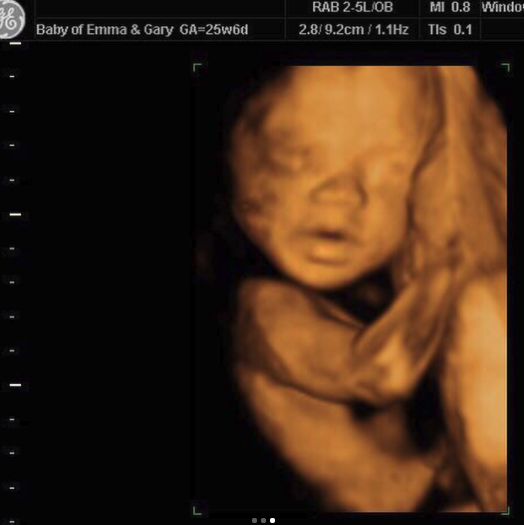

They arrived Thursday evening and we got straight to it, checking well-being and measurements. Their 2D images were fab, with a wonderful side profile. Baby had a good strong heartbeat and was a perfect and healthy size. We then moved on to 4D…and all we can say is that during the scan, baby was not shy. Taking after Mummy and Daddy, baby was pouting, showing off his biceps all combined with an adorable button nose. Baby was very content during the scan, even cracking the odd smile.

“Little Poser”– Gary and Emma were delighted with their images